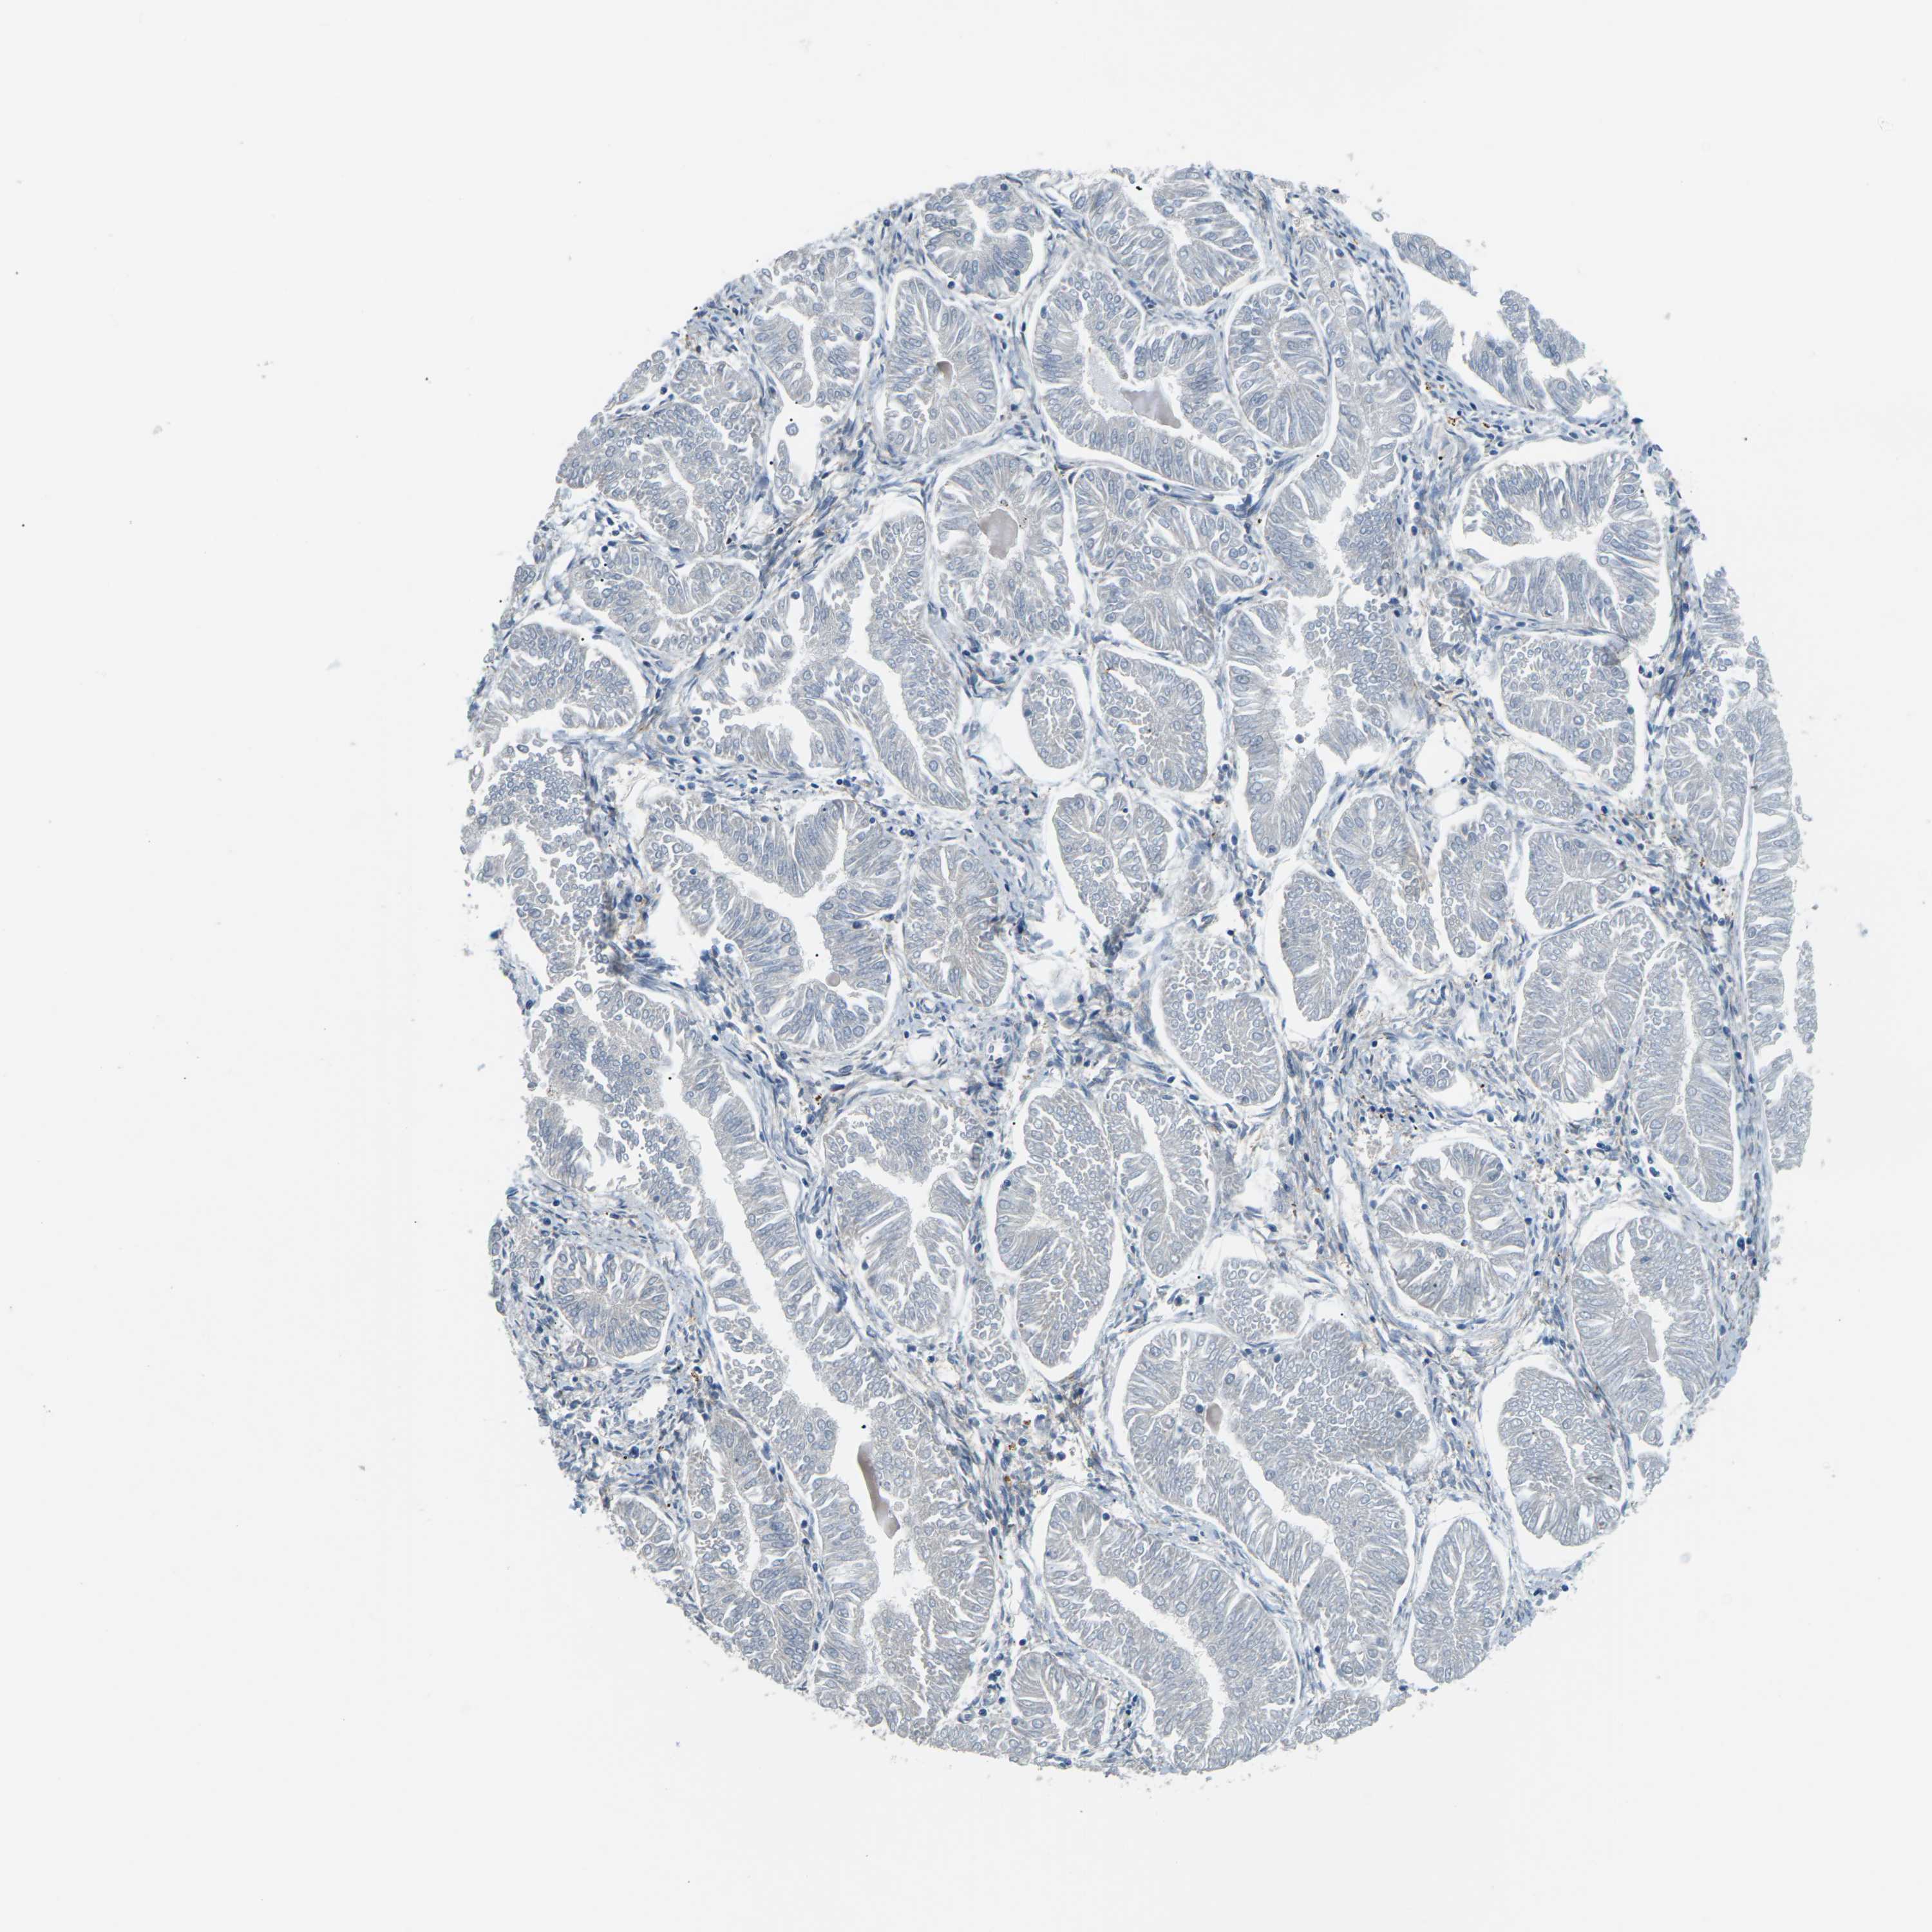

ENDOMETRIAL CANCER - Protein expressioni

A mouse-over function shows sample information and annotation data. Click on an image to view it in a full screen mode. Samples can be filtered based on level of antibody staining by selecting one or several of the following categories: high, medium, low and not detected. The assay and annotation is described here.

Note that samples used for immunohistochemistry by the Human Protein Atlas do not correspond to samples in the TCGA dataset.

Antibody stainingi

Antibody staining in the annotated cell types in the current human tissue is reported as not detected, low, medium, or high, based on conventional immunohistochemistry profiling in selected tissues. This score is based on the combination of the staining intensity and fraction of stained cells.

Each image is clickable and will lead to virtual microscopy that enables deeper exploration of all samples and also displays staining intensity scores, fraction scores and subcellular localization as well as patient and tissue information for each sample.

Antibody HPA014353

Antibody HPA014736

Staining

High

Medium

Low

Not detected

Intensity

Strong

Moderate

Weak

Negative

Quantity

>75%

75%-25%

<25%

None

Location

Nuclear

Cytoplasmic/membranous

Cytoplasmic/membranous,nuclear

Adenocarcinoma, NOS